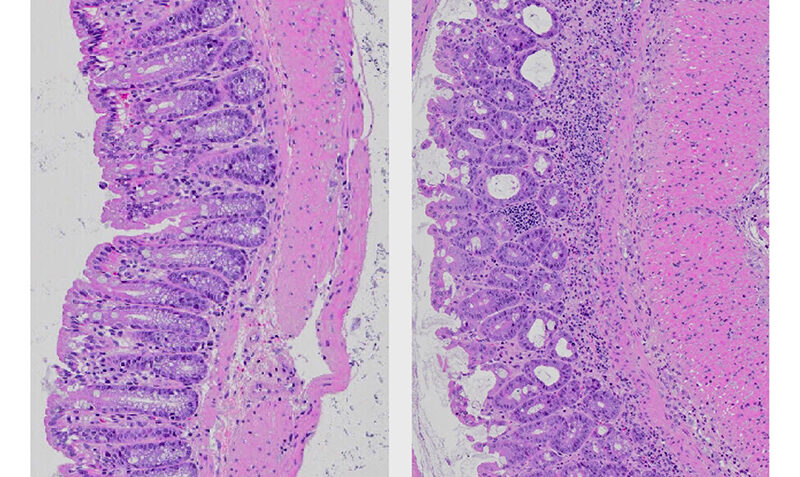

Microscopic images of sections of the colon from mice. Mice fed a normal diet (left) have healthy, well-organised gut tissues. In contrast, mice fed a diet high in fat (right) have disrupted gut tissue, a thickening of the gut wall (pink) and an accumulation of immune cells (purple dots) – clear signs of inflammatory bowel disease.